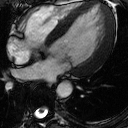

The cardiac MRI scan at the left reveals an enlarged heart, left ventricular hypertrophy (LVH) and scar tissue in the left ventricle wall as a result of Fabry disease. Periodic cardiac MRI scans at 18 months on enzyme replacement therapy (ERT), 24 months on ERT, and 30 months on ERT indicate significant reduction in heart volume and left ventricle wall thickness improving with each subsequent scan. The image at the right shows the same approximately 50-year-old male's heart with normal heart function despite reduced yet persistent LVH. This individual had been on ERT for 5 years at the time of this entry.

Heart complications are common among individuals with Fabry disease and are a key cause of premature death. Cardiac events are caused both by the direct results of Fabry disease and by the secondary results of cardiovascular disease associated with kidney dialysis common among individuals with Fabry disease.

A key symptom of Fabry disease is LVH often without any major outflow obstruction or a history of high blood pressure. These factors associated with the unexplained LVH should alert physicians to search for the underlying cause, in this case, Fabry disease, but often do not lead to a diagnosis. In various studies, approximately 3 to 12% of individuals with unexplained LVH have Fabry disease. Reduced ejection fraction accompanied by clinical signs of congestive heart failure can also be seen in advanced stages of the disease.

Lipid (GL-3) accumulation itself is not a significant contributor to heart enlargement or increased thickness in the left ventricle wall. Other factors including inflammation and dysfunction of hormones acting on the nervous system are thought to be the stimulus for the cardiac hypertrophy (heart enlargement).